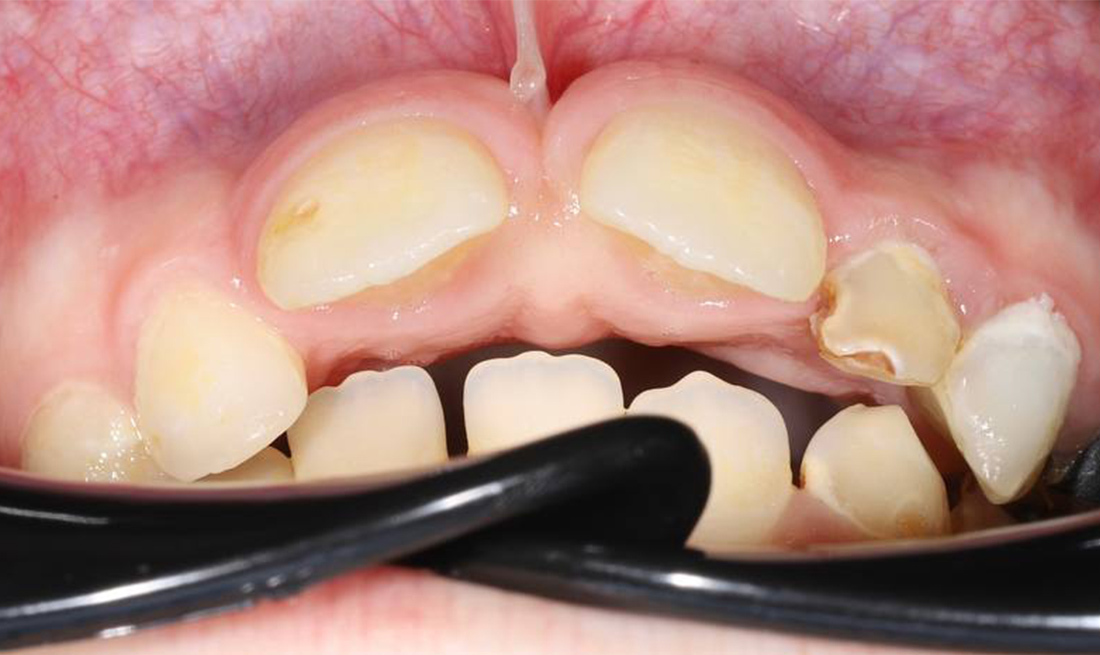

Исправление неправильного прикуса и замена устаревших реставраций для гармоничной улыбки